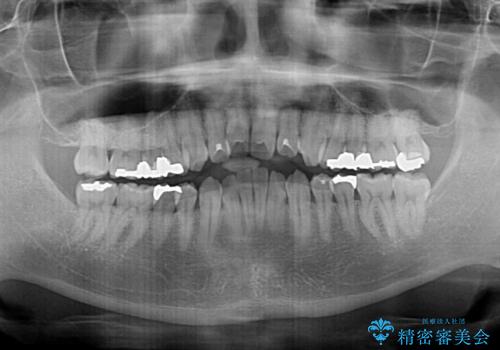

- 奥歯の目立つ銀歯と上下前歯の叢生と隙間を気にして来院された患者様です。

開咬の治療は、前歯を閉じるように動かすとともに、上下臼歯を圧下(骨内にめり込ませる)させることで進めて行きます。

インビザラインは臼歯の圧下を効果的に行えるため、インビザラインを用いて矯正治療を行うこととしました。

銀歯については、矯正治療により咬合関係を改善し、矯正治療後半に修復治療を行うこととしました。